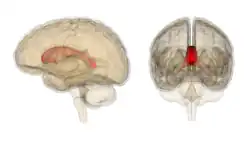

The corpus callosum (Latin for "tough body"), also callosal commissure, is a wide, thick nerve tract, consisting of a flat bundle of commissural fibers, beneath the cerebral cortex in the brain. The corpus callosum is only found in placental mammals.[1] It spans part of the longitudinal fissure, connecting the left and right cerebral hemispheres, enabling communication between them. It is the largest white matter structure in the human brain, about 10 cm (3.9 in) in length and consisting of 200–300 million axonal projections.[2][3]

The corpus callosum forms the floor of the longitudinal fissure that separates the two cerebral hemispheres. Part of the corpus callosum forms the roof of the lateral ventricles.[5]

The corpus callosum has four main parts – individual nerve tracts that connect different parts of the hemispheres. These are the rostrum, the genu, the trunk or body, and the splenium.[4] Fibres from the trunk and the splenium, known together as the tapetum ("carpet"), form the roof of each lateral ventricle.[6]

On either side of the corpus callosum, the fibers radiate in the white matter and pass to the various parts of the cerebral cortex; those curving forward from the genu into the frontal lobes constitute the forceps minor (also forceps anterior) and those curving backward from the splenium into the occipital lobes, the forceps major (also forceps posterior).[4] Between these two parts is the main body of the fibers, which constitute the tapetum and extend laterally on either side into the temporal lobe, and cover in the central part of the lateral ventricle. The tapetum and anterior commissure share the function of connecting left and right temporal lobes.